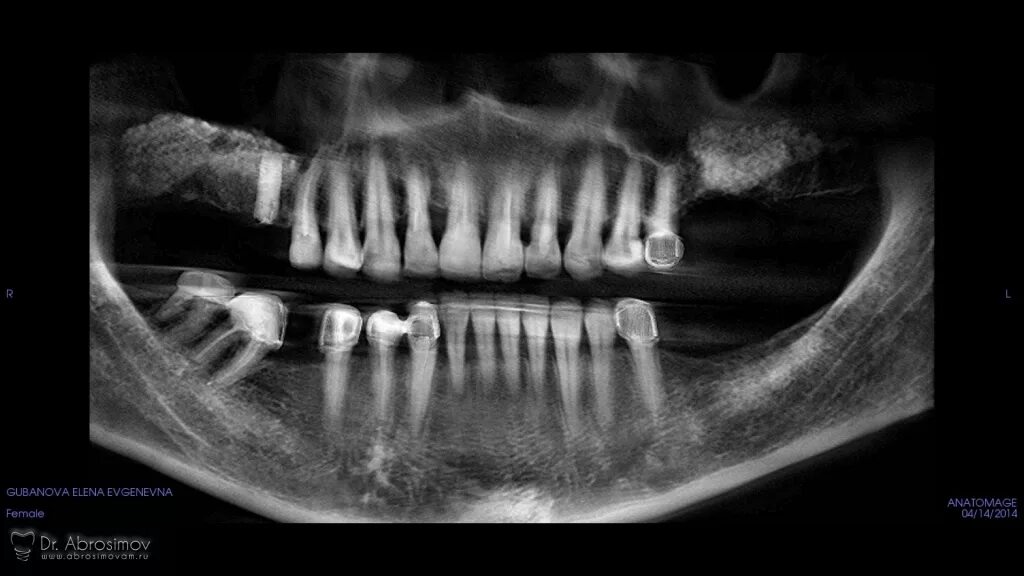

Picasso кт